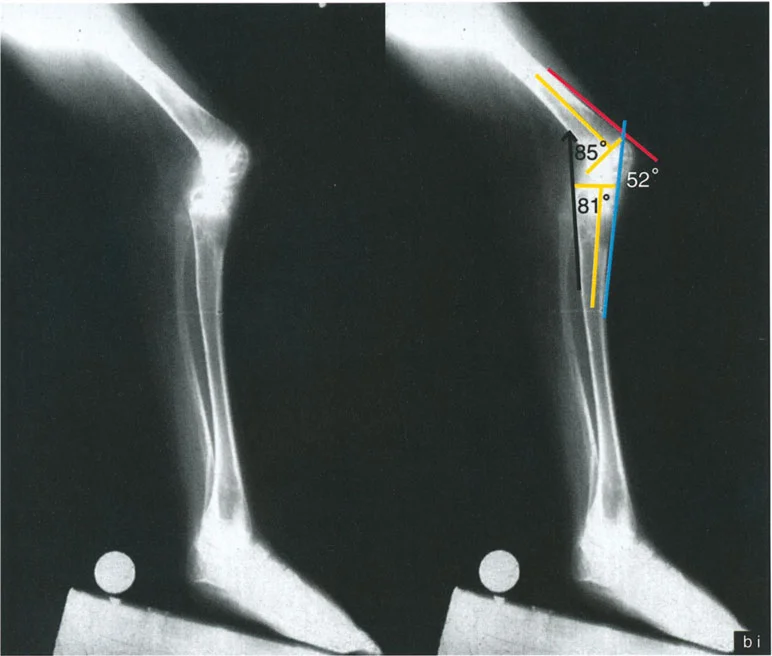

تُعد الأشعة التصويرية ضرورية لتأكيد التشخيص وتحديد مدى الضرر وموقع التشوهات العظمية بدقة:

- الأشعة السينية (X-rays):

- الأشعة الأمامية الخلفية (AP View) والجانبية (Lateral View): تُظهر حالة العظام، تآكل الغضروف (يُلاحظ كضيق في المسافة المفصلية)، وجود نتوءات عظمية (Osteophytes)، وأي تشوهات عظمية واضحة.

- الأشعة السينية الطويلة للطرف السفلي بالكامل أثناء الوقوف (Standing Long-Leg AP View): تُعد هذه الأشعة حاسمة لتقييم المحاذاة الميكانيكية للطرف السفلي بأكمله. تُظهر بدقة درجة الانحراف الأفحج (Varus) أو الأروح (Valgus) وتساعد في تحديد مركز دوران التشوه (CORA).

- الأشعة الجانبية الطويلة للطرف السفلي بالكامل أثناء الوقوف في أقصى بسط (Standing Long-Leg Lateral View in Maximum Extension): تُستخدم لتقييم تحدد حركة الركبة (FFD) والركبة الارتدادية (Recurvatum)، وتحديد ما إذا كان التشوه عظميًا أو ناتجًا عن تقلص في الأنسجة الرخوة.

- التصوير بالرنين المغناطيسي (MRI):

- يوفر صورًا مفصلة للأنسجة الرخوة مثل الغضاريف، الأربطة، الأوتار، والعضلات.

- يساعد في تقييم مدى تآكل الغضروف، وتلف الغضاريف الهلالية، وإصابات الأربطة، ووجود أي سوائل داخل المفصل.

- مفيد بشكل خاص في تحديد أسباب تحدد الحركة أو الارتدادية التي قد لا تكون عظمية.

- التصوير المقطعي المحوسب (CT Scan):

- قد يُستخدم في حالات معينة للحصول على صور ثلاثية الأبعاد للعظام، خاصة في التخطيط لجراحات تصحيح التشوهات المعقدة أو لتقييم دوران العظام.

من خلال الجمع بين الفحص السريري الدقيق والتحليلات التفصيلية للصور الشعاعية، يتمكن الأستاذ الدكتور محمد هطيف من تحديد الأسباب الكامنة وراء آلام الركبة وتشوهاتها، وتصميم خطة علاجية فردية تهدف إلى استعادة وظيفة الركبة وتخفيف الألم.